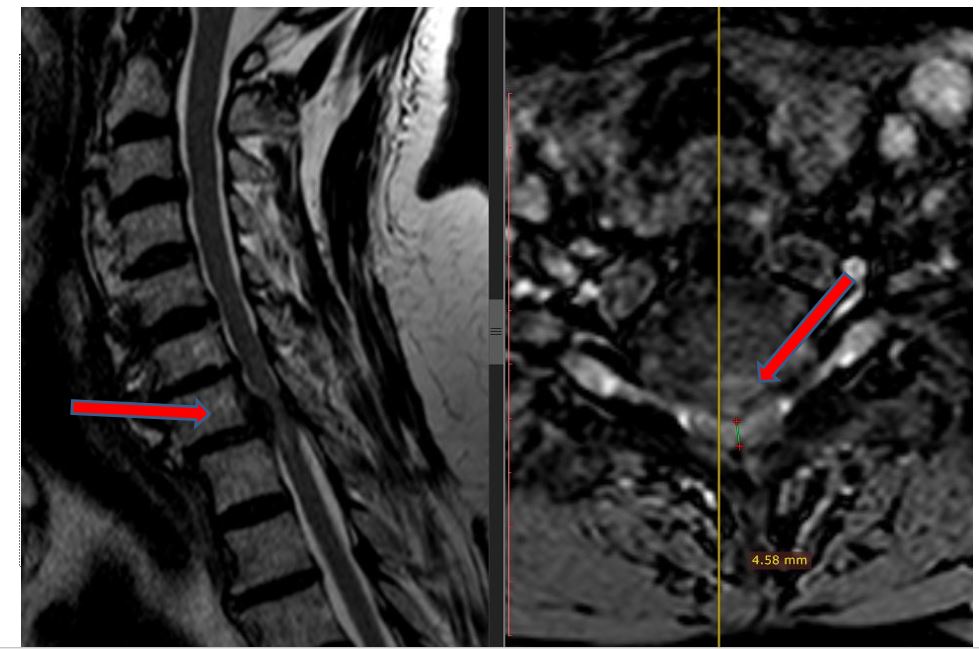

“Kur I.K erdhi te ne, veç të tjerash, kishte humbje të ekuilibrit gjatë ecjes, dhembje në të katër gjymtyrët, mpirje sidomos në këmbë (e djathta më shumë) dhe inkontinencë urinare. Rezonanca magnetike zbuloi një shtypje të fortë të palcës kurrizore në vertebrat C6-7 dhe C7-T1 të qafës. Ai gjithashtu kishte hiperostozis të segmentit cervikal të qafës gjë që i kishte bllokuar lëvizjen në të gjitha nyjet e saj. Sinjalet e shtyllës kurrizore kishin ndryshuar dhe nëse nuk do të operohej në kohë, do të ishte paralizuar plotësisht në të dyja këmbët dhe pjesërisht në të dyja duart”, tregon Prof. Dr. Kamil Cagri Kose.

Kirurgu i talentuar dhe me shumë eksperiencë tregon detajet e operacionit delikat: “Kryem korpektomi në vertebrën C7 dhe u hoq kocka e ngjeshur si dhe struktura të diskut. Gjithashtu u vendos një mbështetëse prej titani për të zgjidhur problemin dhe për të fiksuar segmentin në mënyrë që situata të mos përsëritet më”.